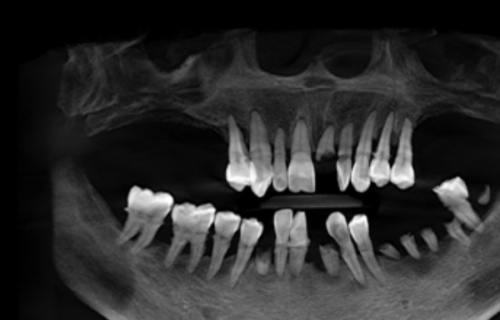

在进行种植牙手术之前,全方面的术前评估是必不可少的。医生会先给你做一个口腔检查,看看你的牙齿和牙龈的具体情况。同时,还会借助影像学评估,比如拍X光片或者进行三维影像重建,这样就能清楚地了解牙槽骨的形态、密度等信息。另外,全身健康状况分析也特别重要,医生要排除一些不适合种植牙的情况,像重度牙周病、未控制的糖尿病等。有时候还会让你做血检查,进一步了解你的身体状况。通过这些检查和分析,医生就能为你确定更适合的种植方案啦。